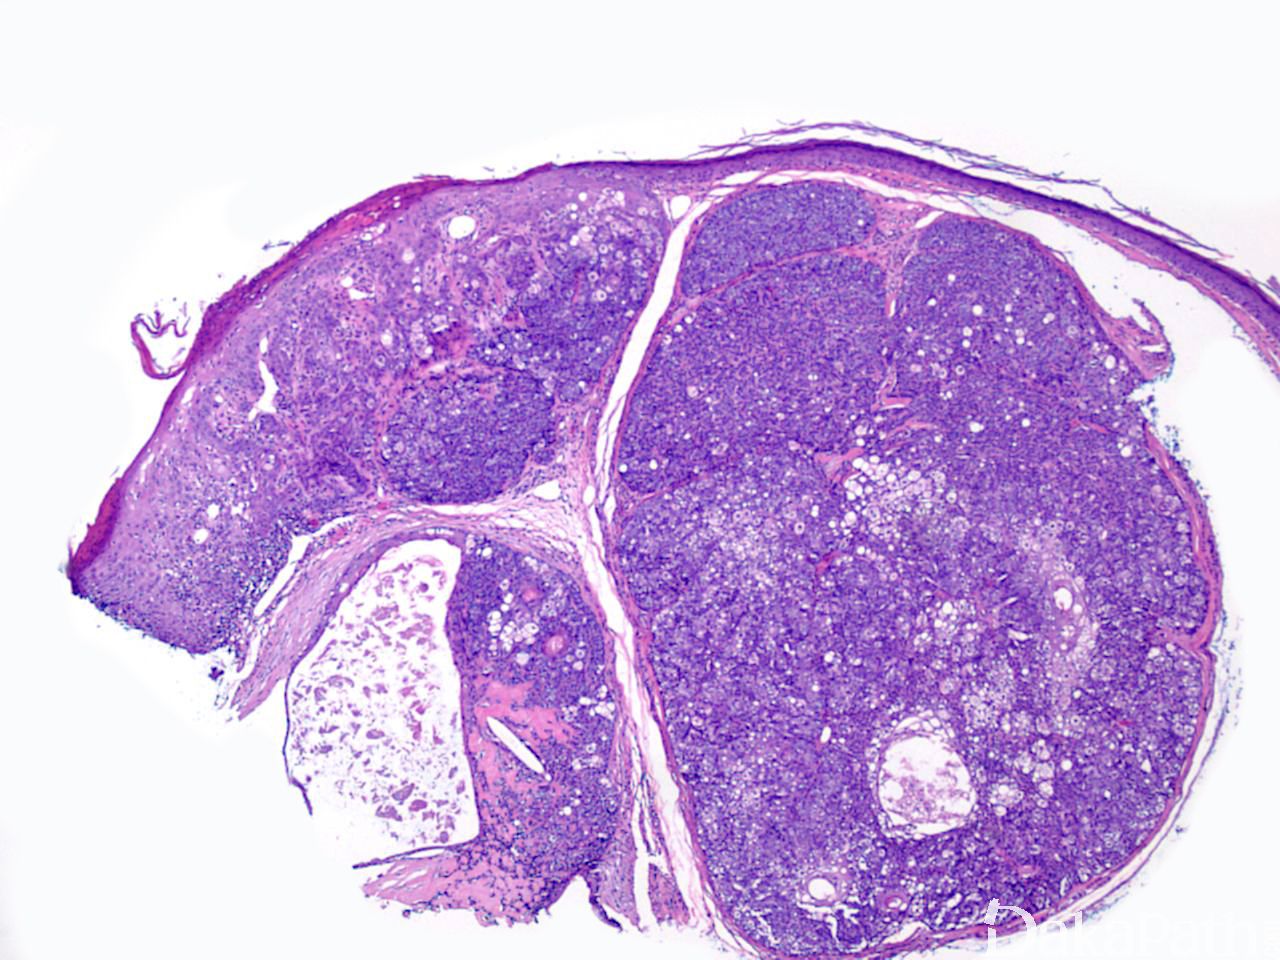

肿瘤境界清楚, 位于真皮内,偶与表皮相连接;

镜下见多数形状不规则的瘤细胞团,细胞团块的中心为成熟脂肪细胞,基底样生发细胞常位于瘤细胞团块的边缘,基底样生发细胞多于成熟脂肪细胞;

成熟的皮脂腺结构少见;

可见有丝分裂像,但无病理性核分裂像,也无细胞异型性。